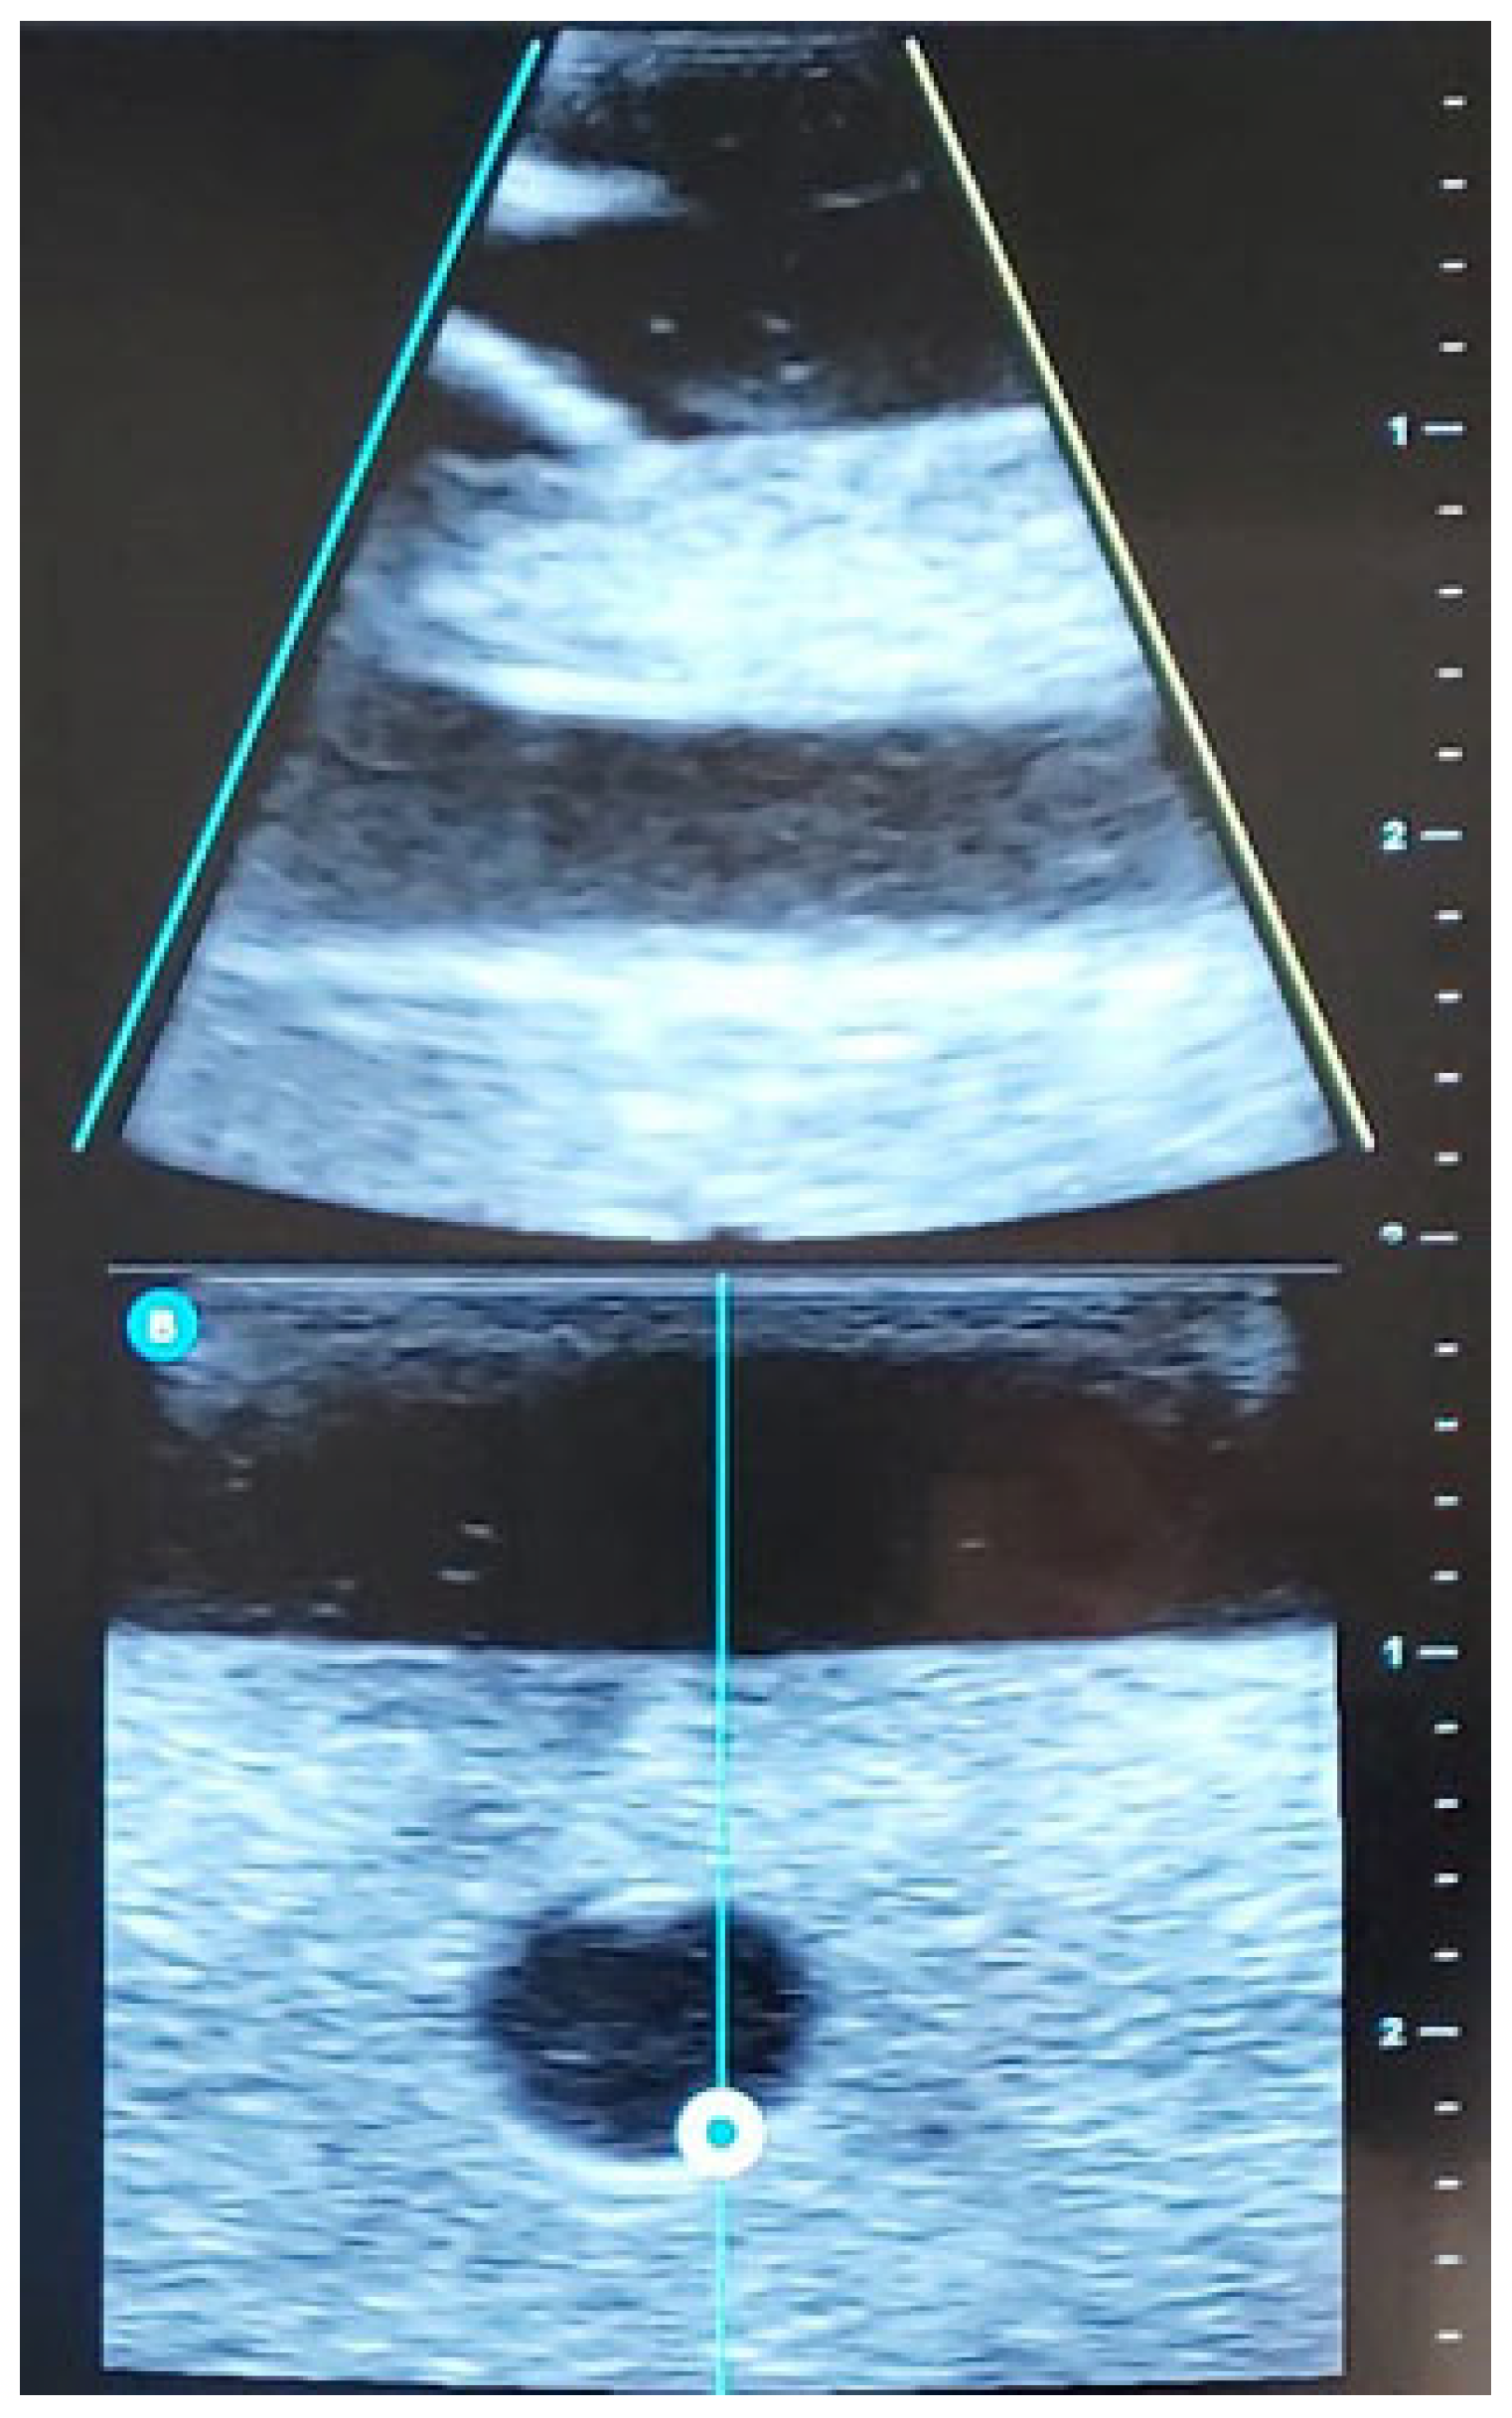

| STEP 3 | Ultrasound-guided examination of the limb to be punctured (RaPeVa):

| STEP 4 | Selection of an appropriate vessel (depth, diameter, and patency):

| STEP 6 | Ultrasound-guided puncture: